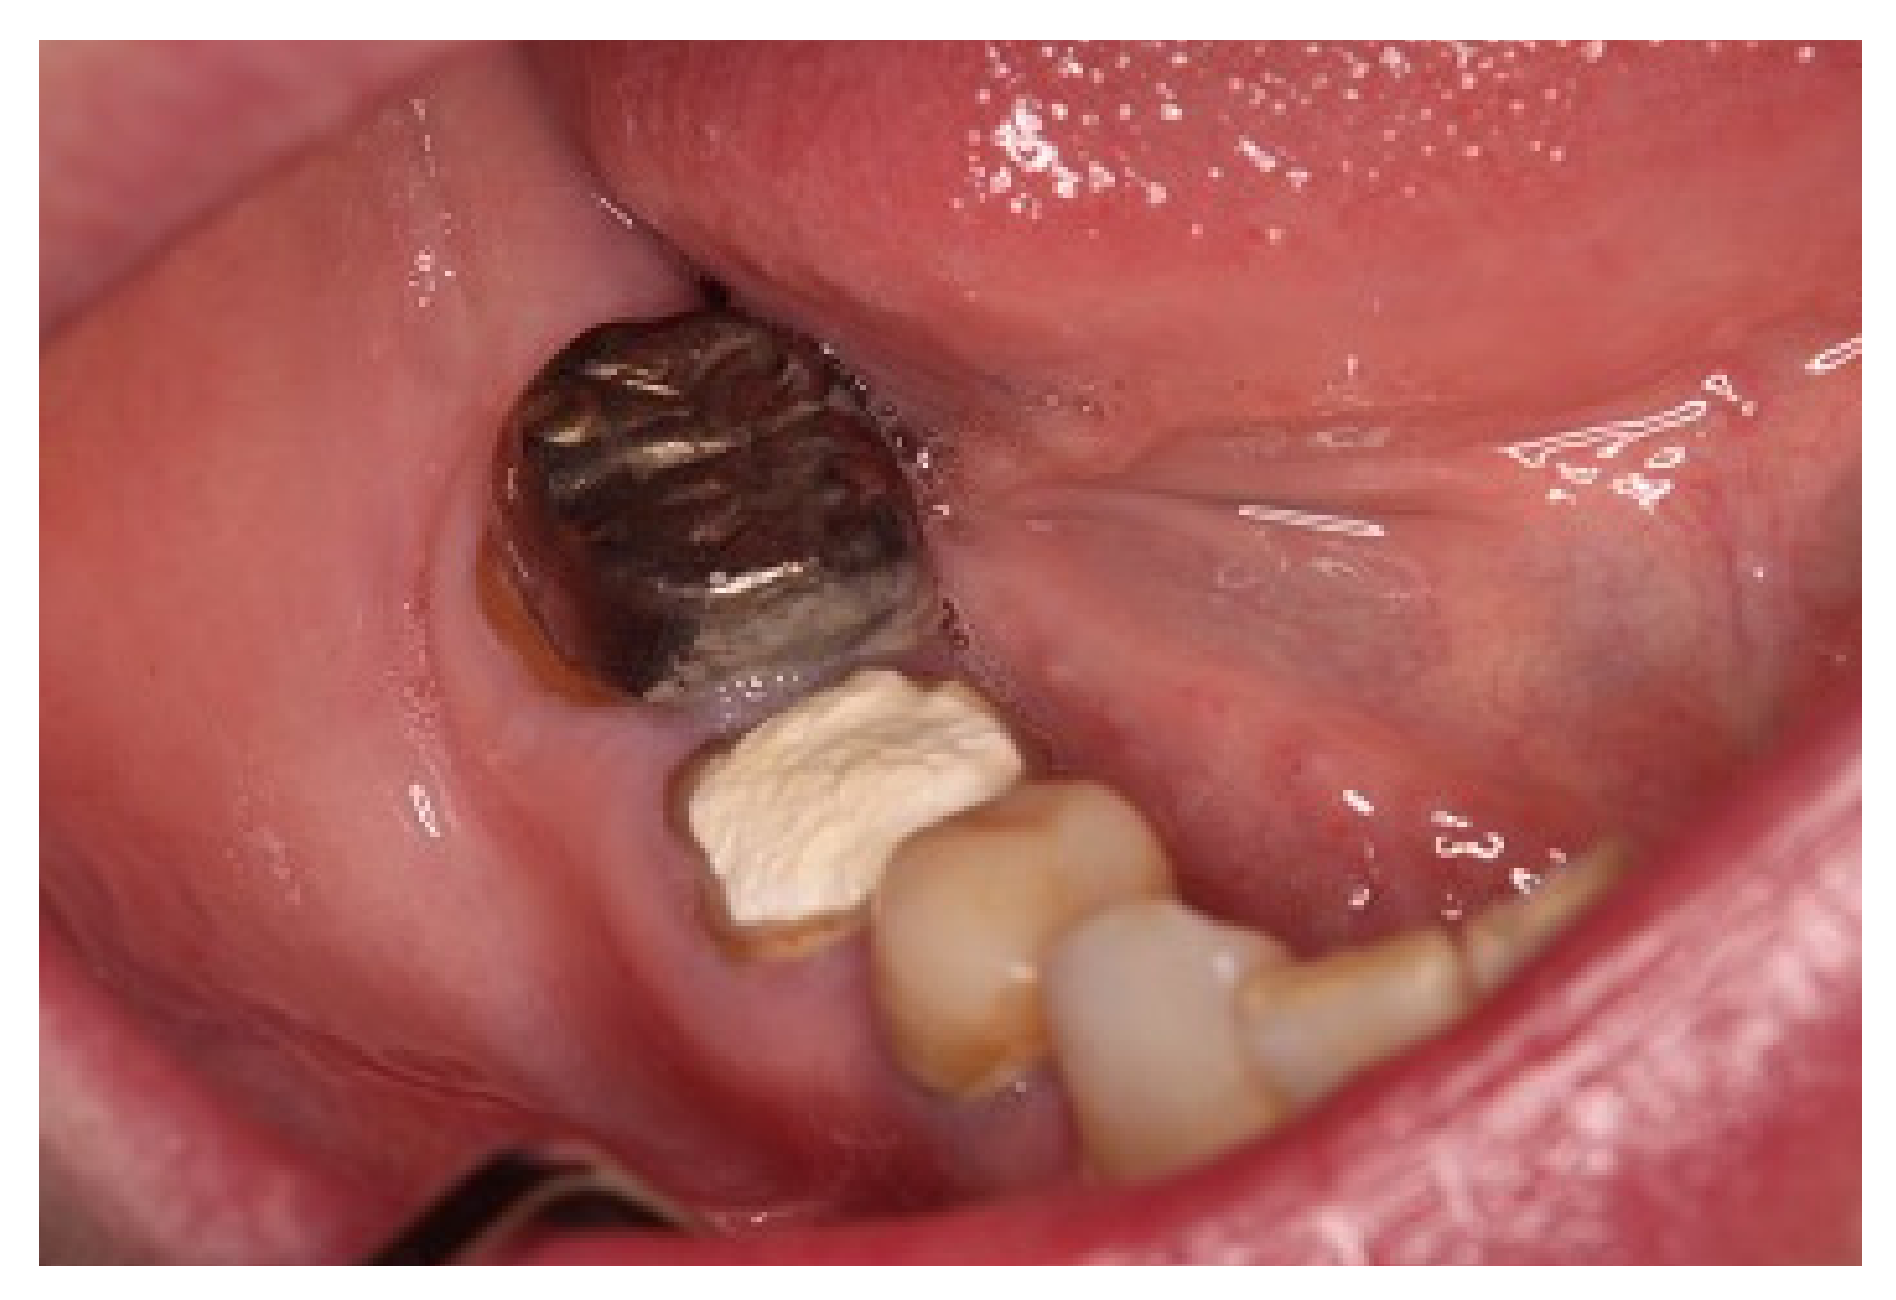

3. Case Report